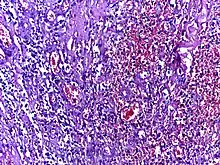

![]() | Dysgerminoma | Dysgerminoma characterized by uniform cells resembling primordial germ cells separated by fibrous septa with lymphocytes. | Category: Histopathology of ovarian dysgerminoma | Ovarian dysgerminoma |